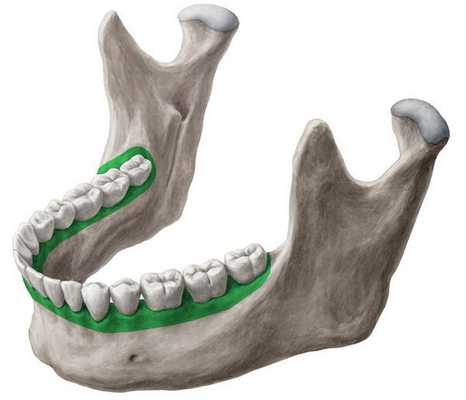

В отличие от предыдущих случаев, у данной пациентки хирургический этап включал операцию только на нижней челюсти. В ходе операции мобилизованный срединный фрагмент перемещался кзади. При этом объем перемещения слева был вдвое больше, чем справа. По сравнению с вышеописанными случаями, у данной пациентки были самые неудачные условия и самый неблагоприятный, с точки зрения риска развития рецидива, прогноз. Проведение операции на нижней челюсти при мезиальном прикусе является самым спорным решением с позиций долговременной стабильности результата. Следуя такой логике, давление языка в условиях уменьшившегося объема полости рта должно привести к возникновению рецидива аномалии, особенно при «недостаточно надежной стабилизации» зубных рядов.

Полученные данные свидетельствуют о максимальной выраженности перестройки зубных рядов по отношению к рассмотренным вариантам. Суть этих изменений состоит в увеличении высоты альвеолярных частей челюстей.

Операция проводится при установленной в полости рта пациента эластичной проволочной дуге прямоугольной формы максимального сечения. В послеоперационном периоде на фоне повышения пластичности костной ткани дуги полностью реализуют заложенные в них угловые характеристики паза замка (брекета). Помимо постоянно действующего на зубы давления дуги, используются межчелюстные эластичные резиновые тяги. Совокупное действие этих факторов приводит к активной перестройке тканей пародонта, причем пародонта всех зубов обоих зубных рядов. Тяга мышц, давление языка, воздействие вектора межчелюстных эластиков вызывают направленную перестройку альвеолярных частей, соответствующую новым условиям функционирования зубочелюстной системы. Отсюда столь выраженные изменения.

Наш опыт показал, что при условии достижения нейтрального соотношения челюстей, создания множественных окклюзионных контактов и внимательного наблюдения пациента в послеоперационном периоде, рецидив аномалии не происходит ни при использовании «мягких» термоактивных дуг, ни при использовании «жестких» стальных. Длительность использования стальных дуг перед операцией также не имела существенного значения. Во всех случаях в послеоперационном периоде происходит перестройка зубоальвеолярных частей челюстей. Но за счет мобилизации компенсаторных ресурсов зубочелюстной системы окклюзионные контакты удается сохранить. При этом положение зубов претерпевает изменения, которые достигают максимума при использовании в послеоперационном периоде дуг на основе никелид-титанового сплава.